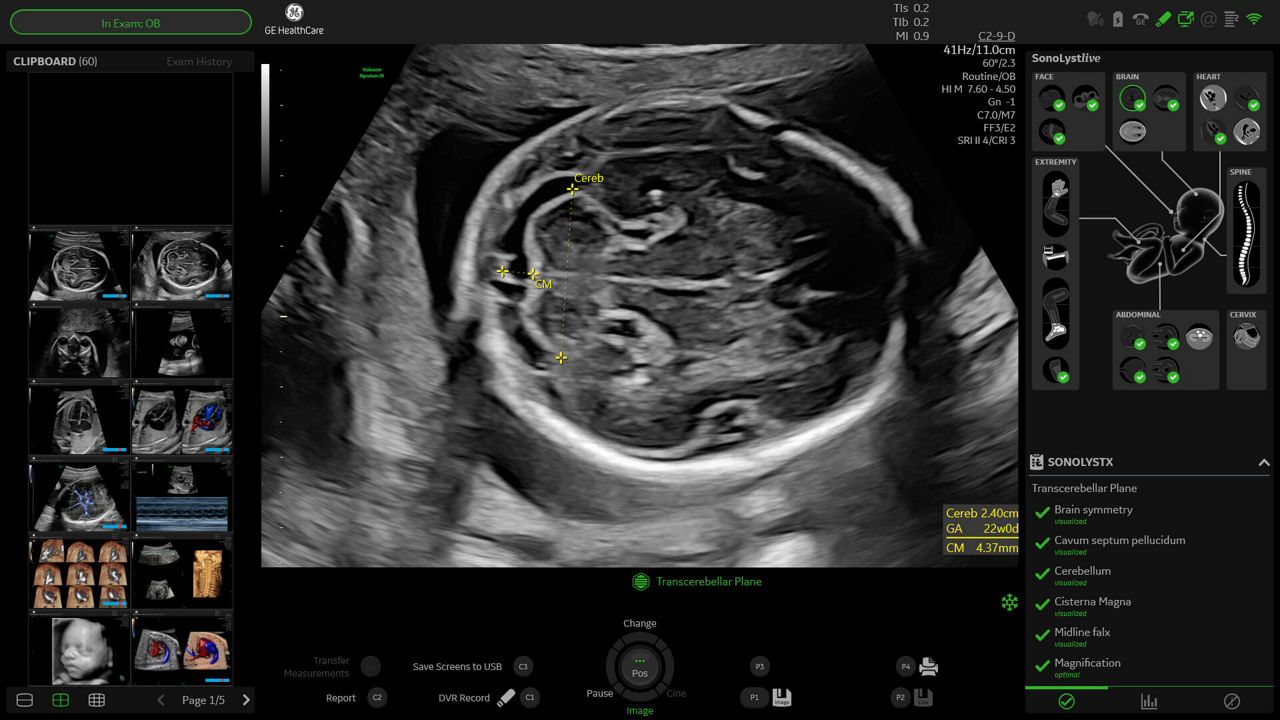

SonoLyst

SonoLyst* reduces the time to complete the standard ISUOG 2nd trimester exam requirements by 40%. And with SonoLyst live, it means no more stopping to freeze, annotate, or store.

fetalHS

Reduce time to assess fetal heart by 48% with fetalHS. fetalHS provides a step-by-step guidance that uses AI to help identify fetal situs and normal fetal heart anatomy using the 4-Chamber Heart, 3-Vessel View/3-Vessels and Trachea View, and Cardiac Axis.